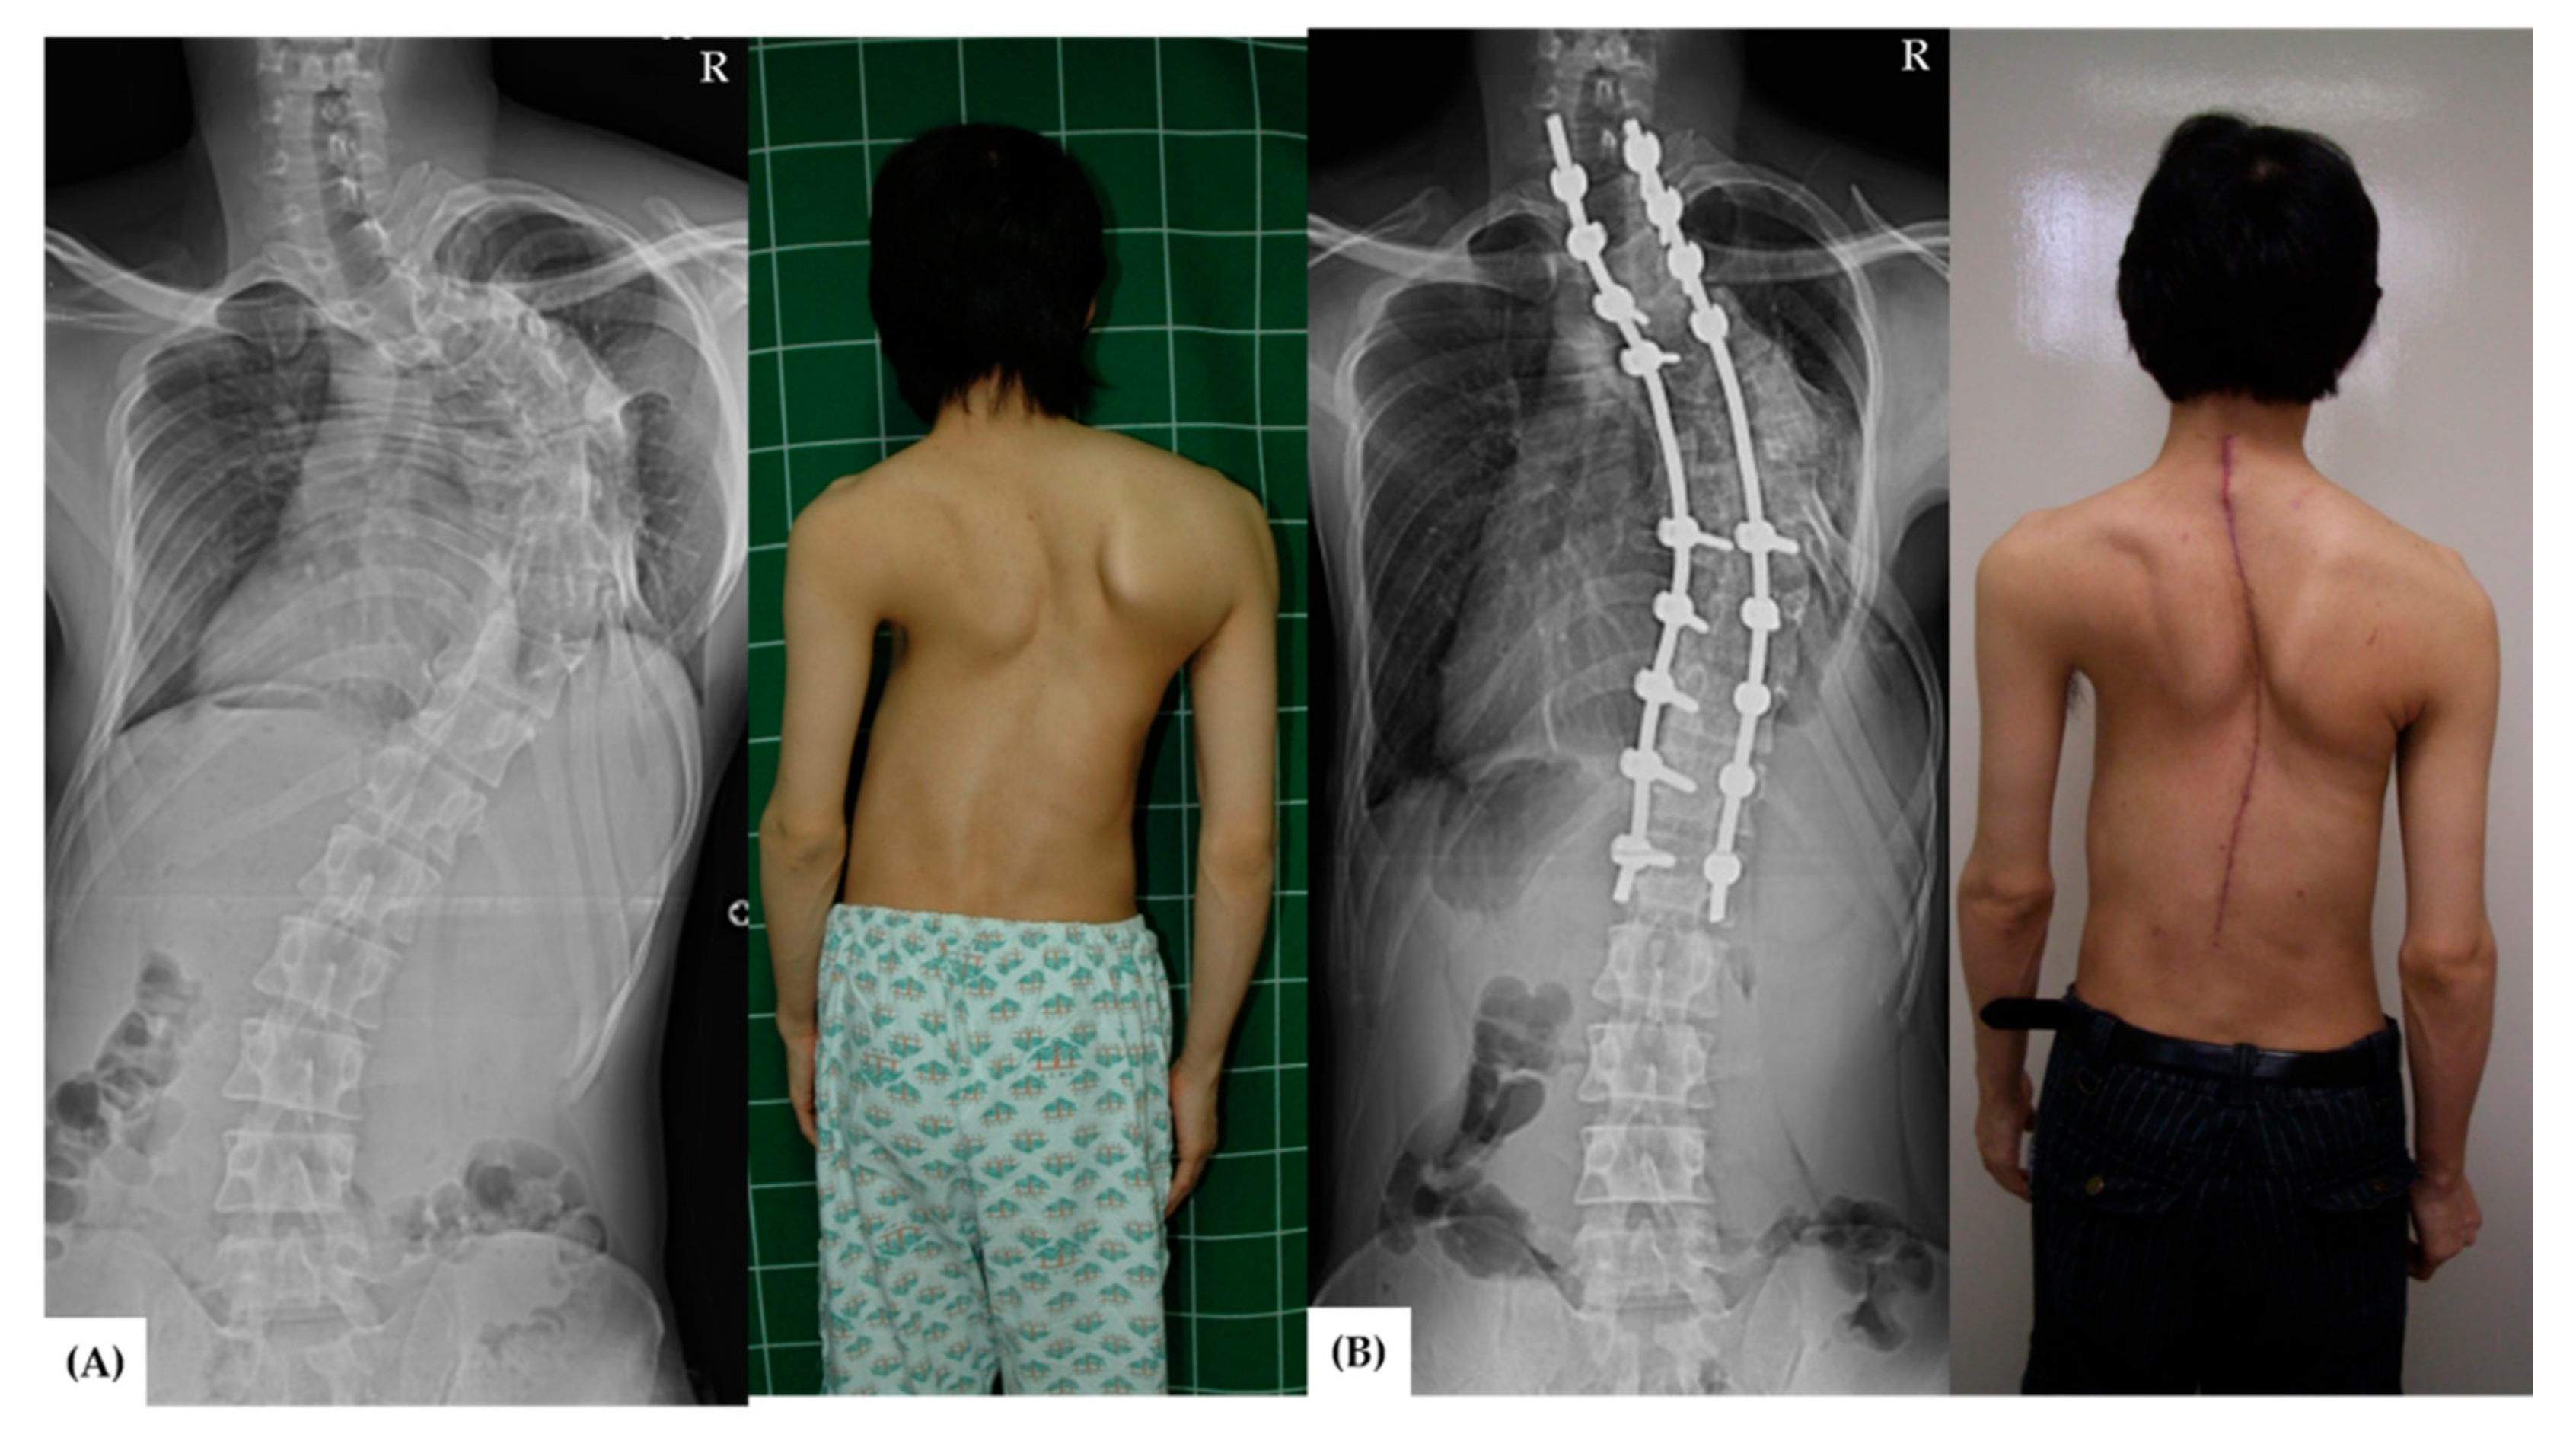

- Riley, M.S.; Lenke, L.G.; Chapman, T.M., Jr.; Sides, B.A.; Blanke, K.M.; Kelly, M.P. Clinical and radiographic outcomes after posterior vertebral column resection for severe spinal deformity with five-year follow-up. J. Bone Jt. Surg. Am. 2018, 100, 396–405. [Google Scholar] [CrossRef] [Green Version]

- Saifi, C.; Laratta, J.L.; Petridis, P.; Shillingford, J.N.; Lehman, R.A.; Lenke, L.G. Vertebral column resection for rigid spinal deformity. Glob. Spine J. 2017, 7, 280–290. [Google Scholar] [CrossRef]

- Chang, D.G.; Yang, J.H.; Lee, J.H.; Kim, J.H.; Suh, S.W.; Ha, K.Y.; Suk, S.I. Congenital scoliosis treated with posterior vertebral column resection in patients younger than 18 years: Longer than 10-year follow-up. J. Neurosurg. Spine 2016, 25, 225–233. [Google Scholar] [CrossRef] [Green Version]